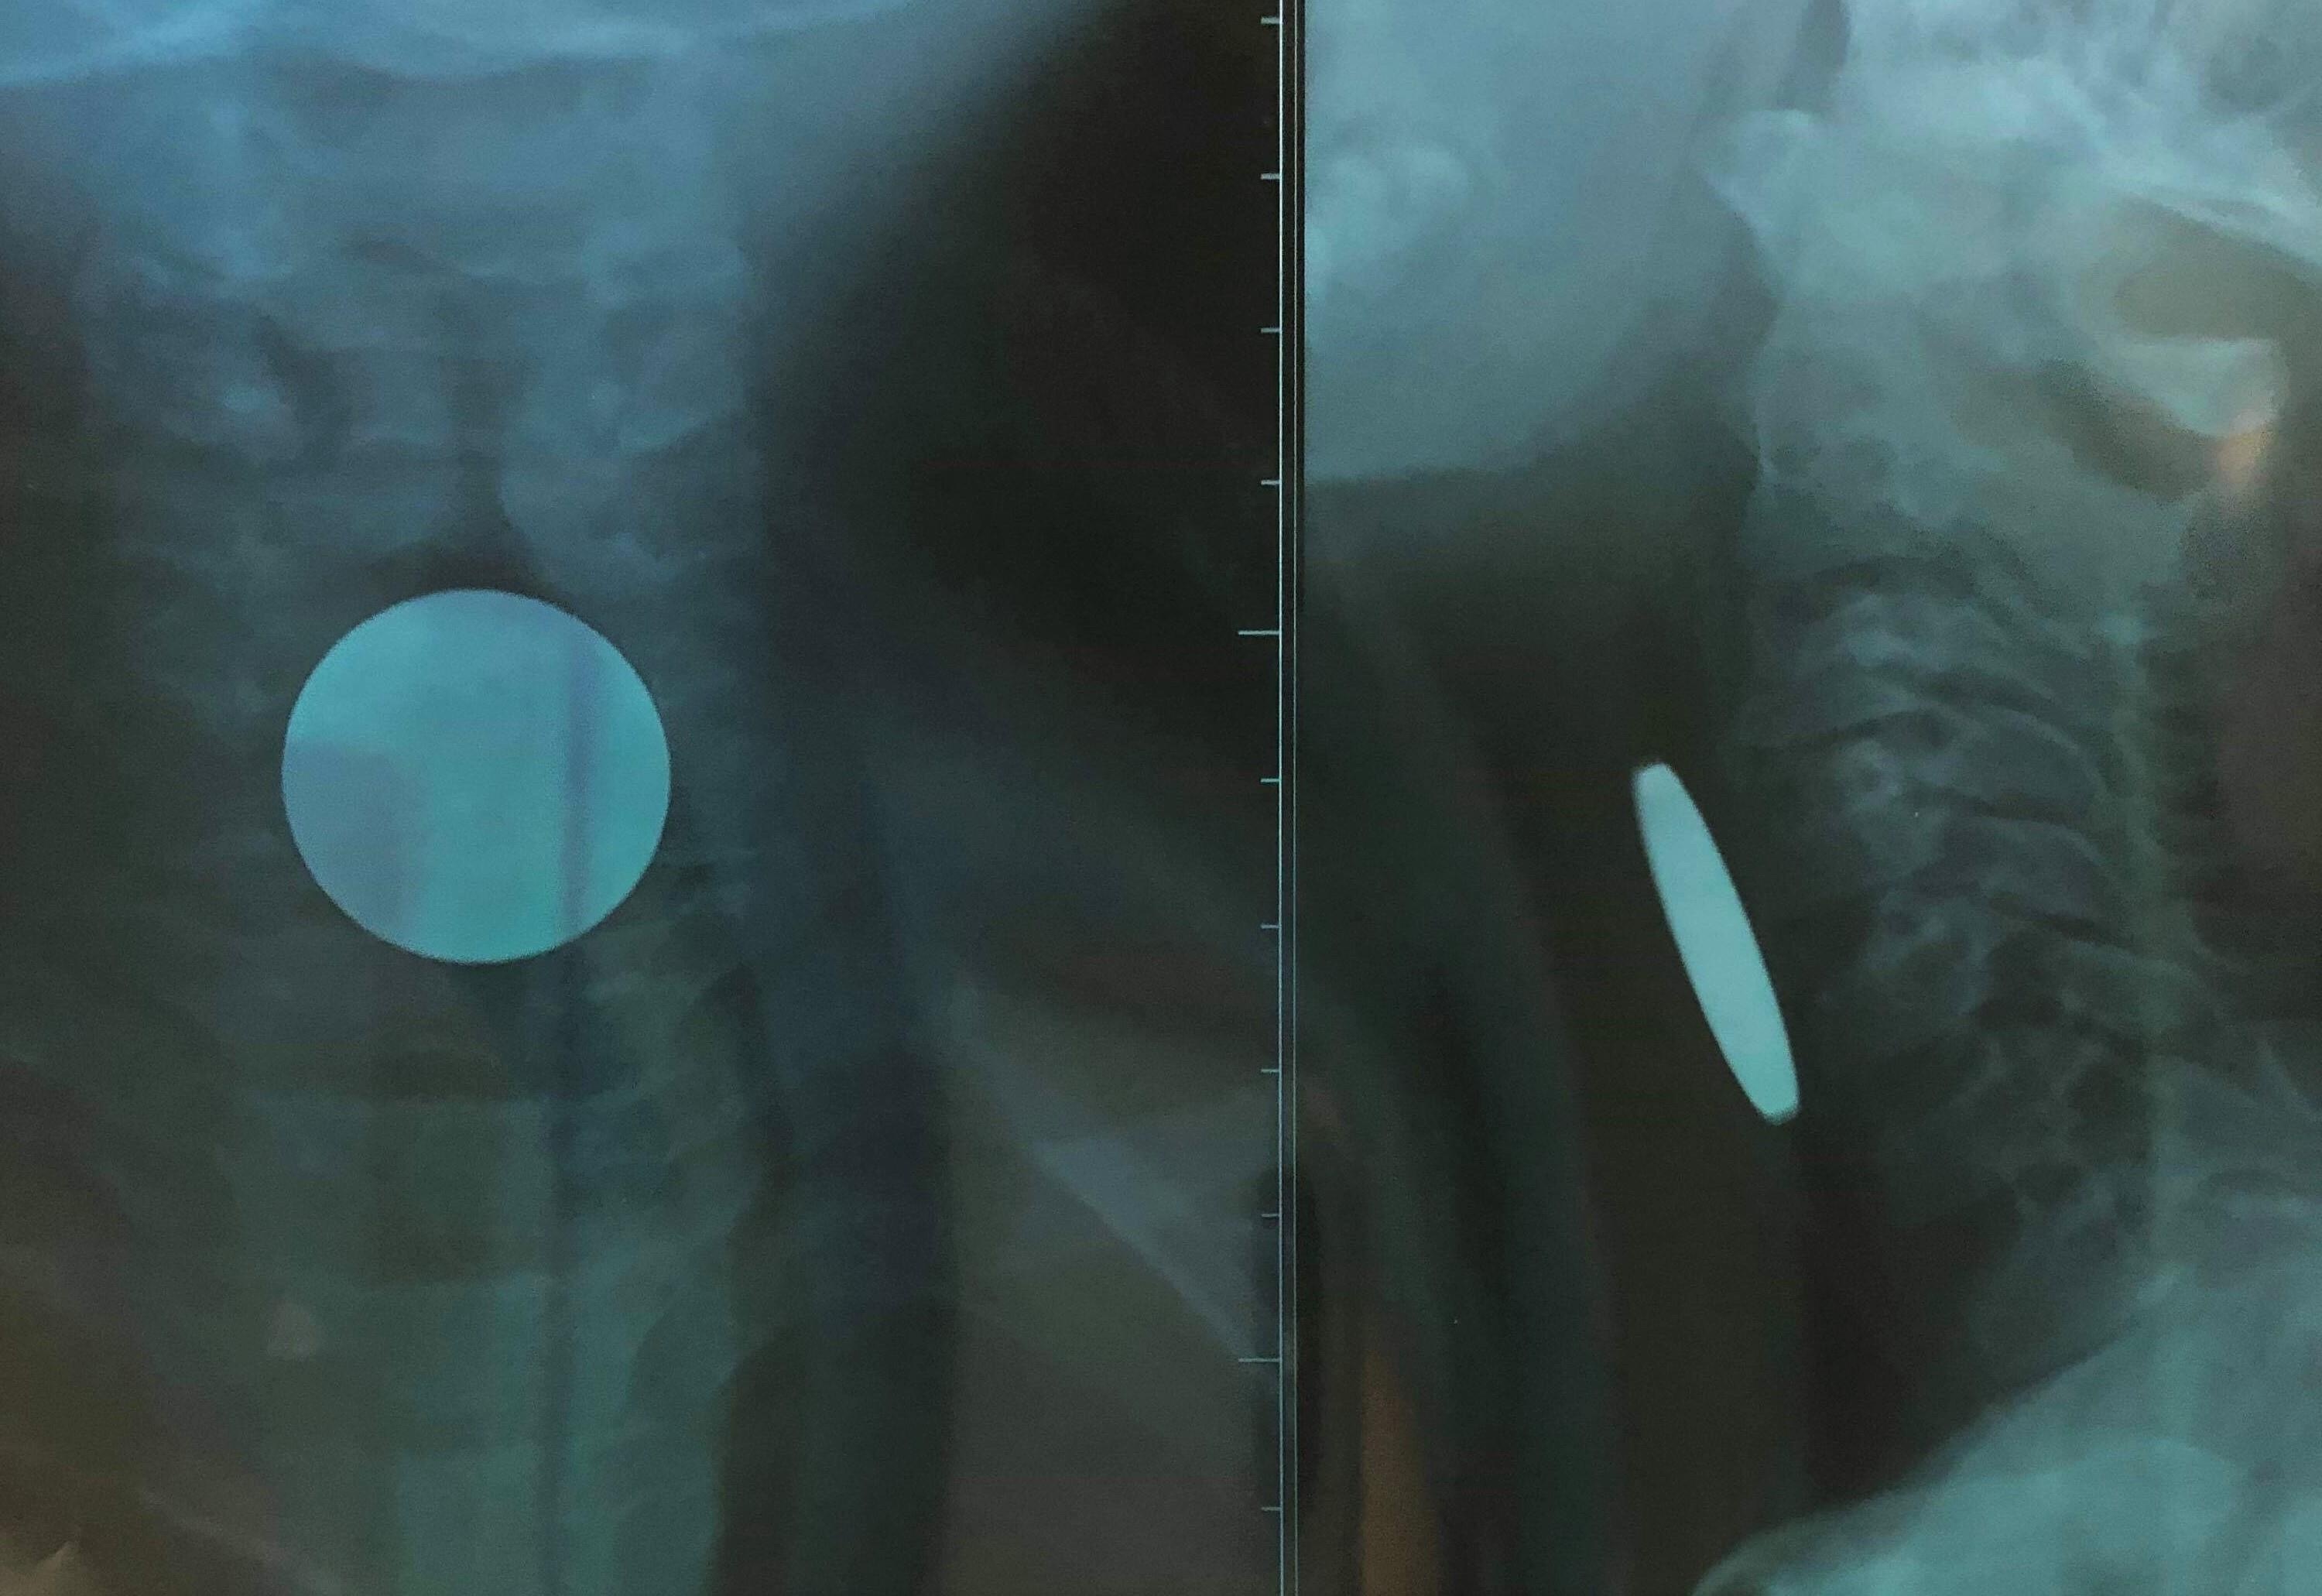

| Hình ảnh đồng xu đoạn thực quản cổ trên phim X-quang |

Bác sĩ Nguyễn Hoàng Tùng, khoa Tai Mũi Họng, cho biết bệnh nhi vào viện trong tình trạng toàn thân ổn định và bé kêu đau vùng cổ. Các bác sĩ tiến hành thăm khám và chụp X-quang, kết quả cho thấy bé bị dị vật (đồng xu) đoạn thực quản cổ có đường kính 24 mm.